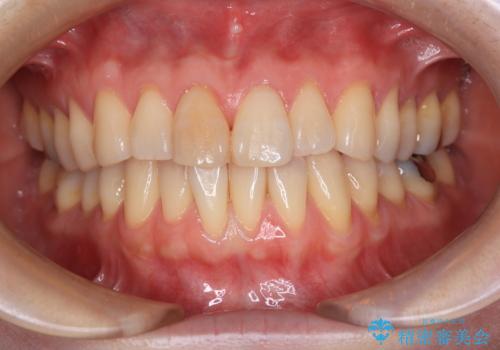

[マルチブラケットで後方移動] ワイヤー矯正で行う噛み合わせの改善